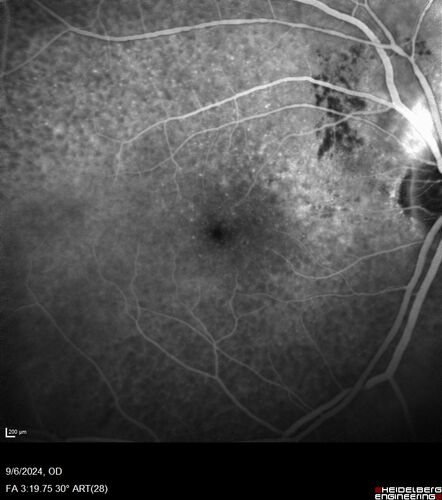

Peripapillary CNVM No Treatment

85 year old with peripapillary CNVM watched for many years.